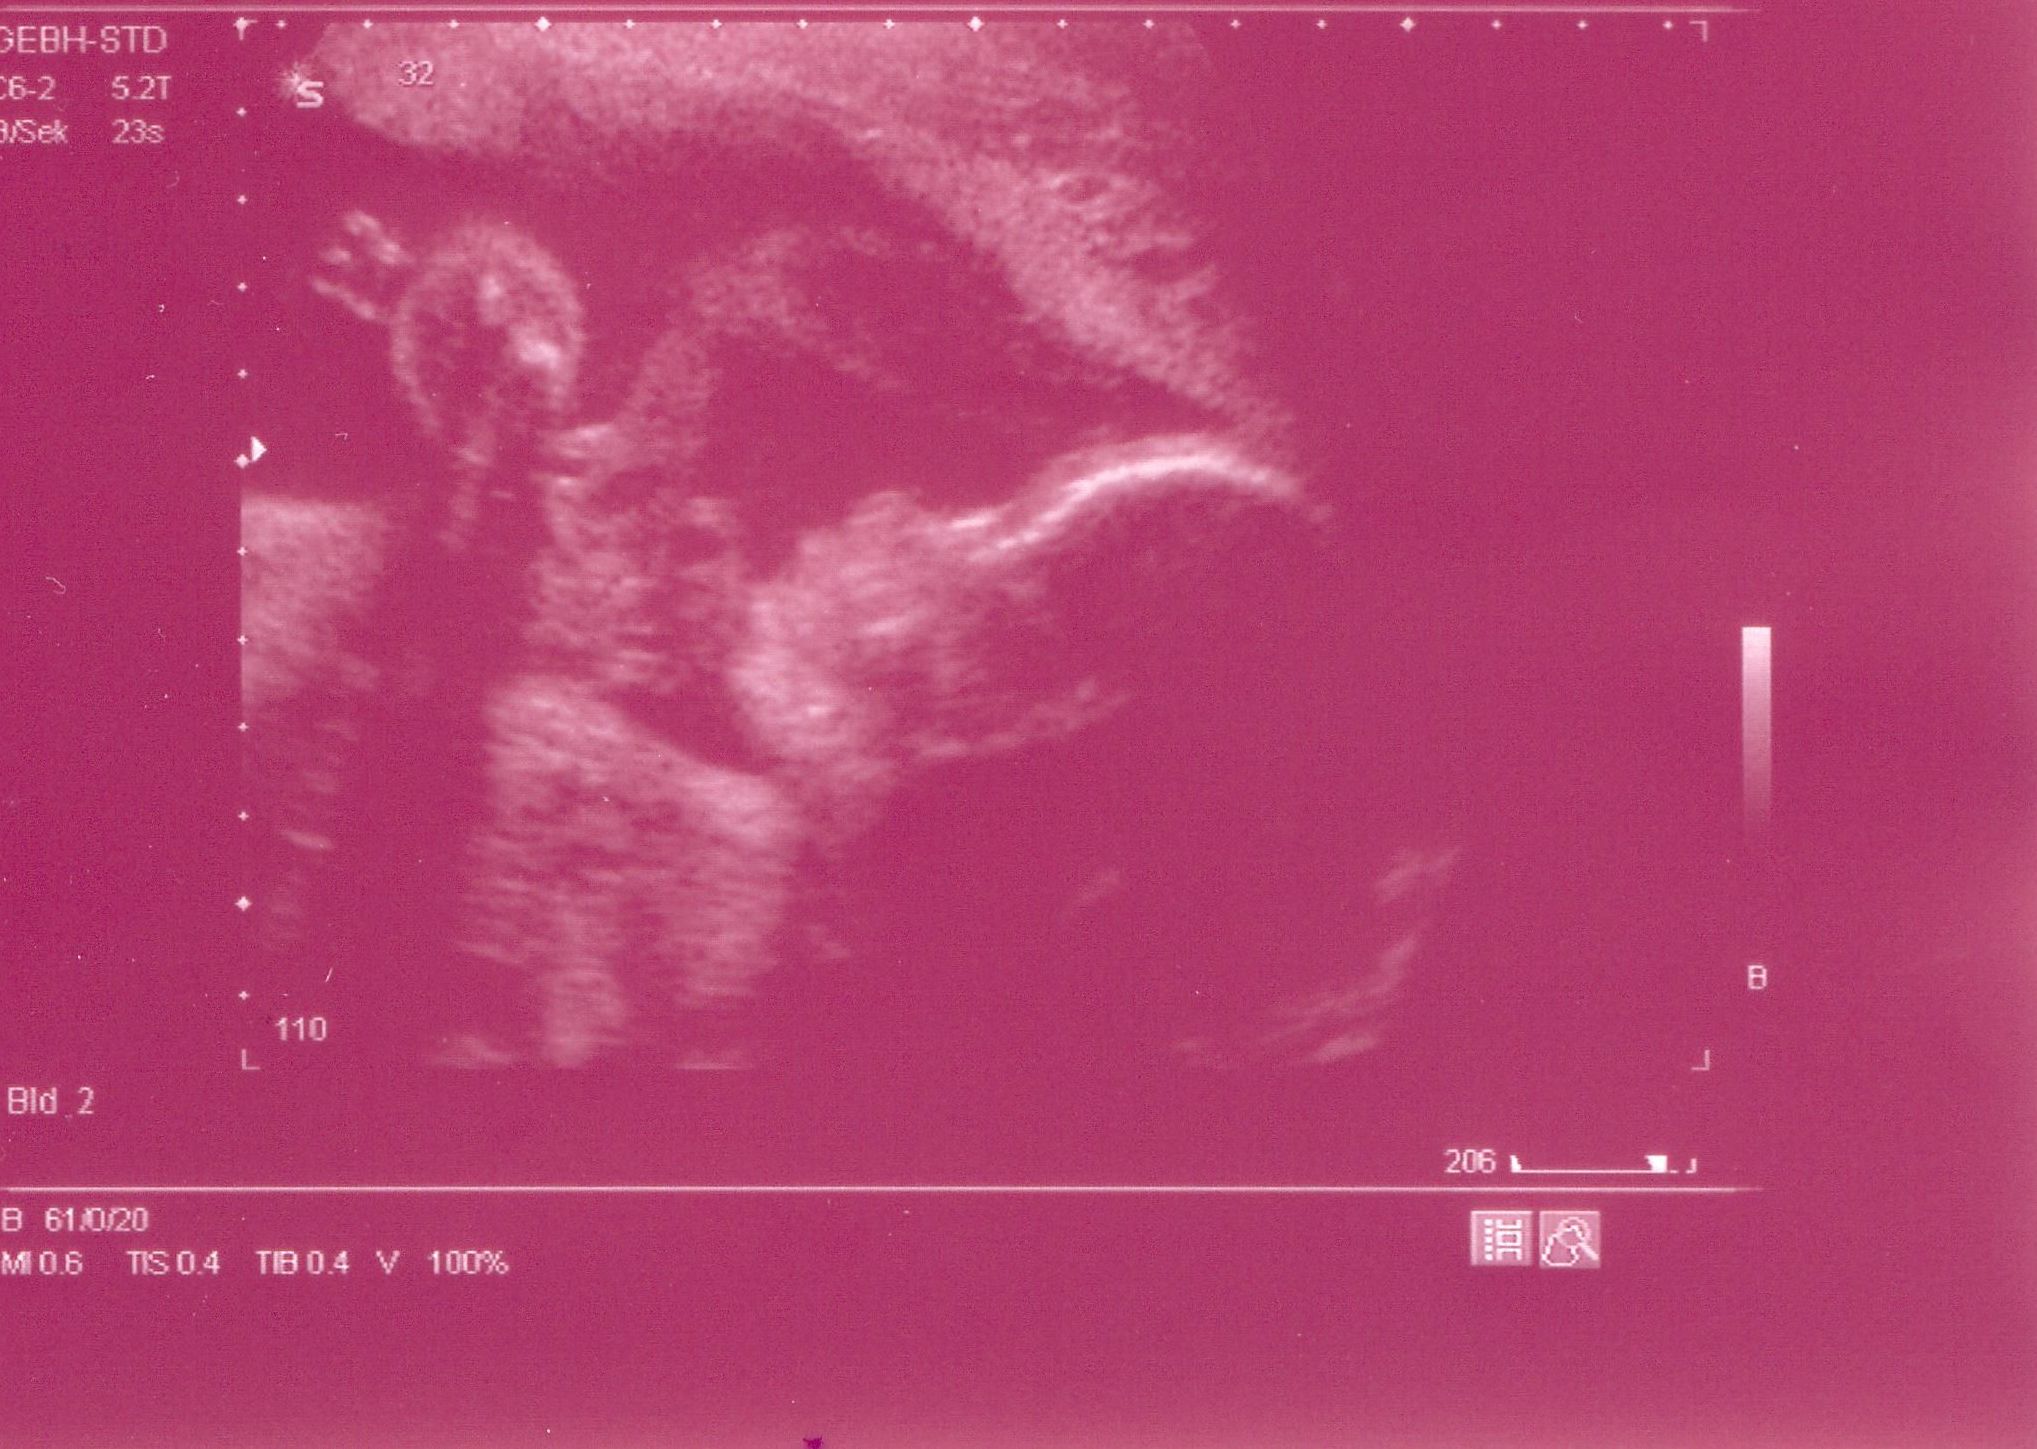

Mir geht es gut und unser Knödelchen hat sich als Mädchen geoutet...sie ist zwar etwas zu leicht und klein , aber sonst scheint alles OK.

Hier mal ein neues US-Bild (Sie spielt da gerade mit der Nabelschnur)